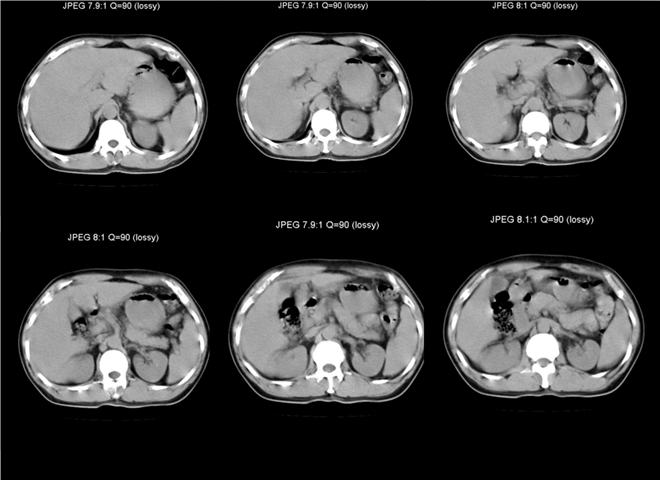

13_CT增强扫描